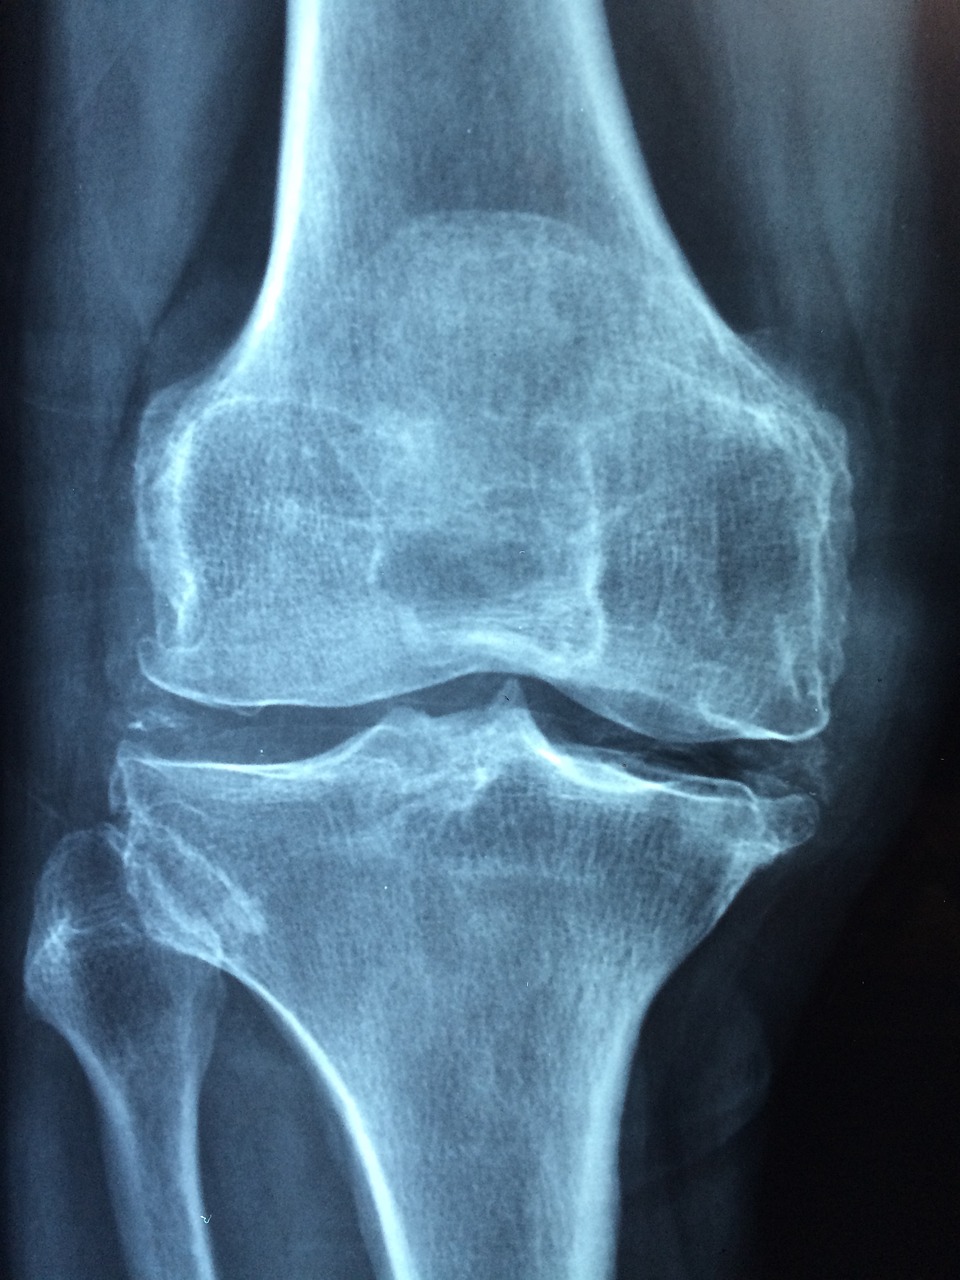

나이가 들수록 무릎관절은 다양한 원인으로 손상되기가 쉽습니다. 무릎의 손상정도가 작다면 약물, 주사, 물리치료 등 보존적 요법으로 치료가 가능하지만 만약 무릎의 손상정도가 강하고 보존적 치료가 어렵고 환자가 일상생활에서의 어려움을 느낄정도로 고통스럽다면 무릎 인공관절 수술을 고려하는 것이 좋습니다. 무릎인공관절수술은 말 그대로 손상된 무릎관절을 제거하고 그 자리를 인공관절(무릎) 기구로 대체하는 수술입니다. 그렇기 때문에 통증을 야기하는 문제 부위를 제거하기 때문에 통증의 근본적인 원인을 해결한다는 점에서 통증을 없애는 가장 확실한 치료방법입니다.